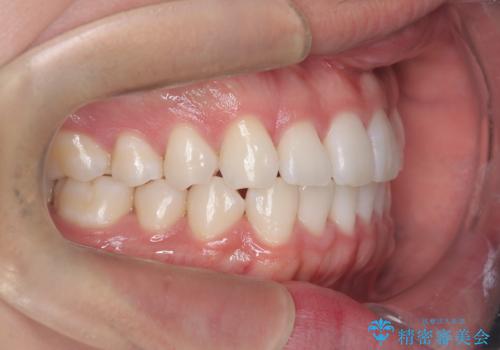

歯のデコボコを治したい|インビザラインで綺麗な歯並びに!|矯正期間は6ヵ月!

インビザラインで叢生の改善を行いました。

歯は抜かずに、拡大と少しのIPRで並べました。

矯正期間は半年です。

綺麗な歯並びを手に入れ大変ご満足していただきました。